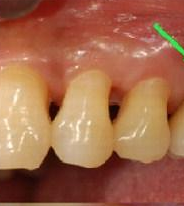

혐 주의

치아 사진 주의

왼쪽은 치석이 굉장히 많이 엄청 쌓인거야.

보통은 치아안쪽에 치아 틈이없이 무언가가 하얗게 채우고

있을거야. 오른쪽은 그걸 제거한 사진이고 .

이사진은

이미 많이 진행된 상태야